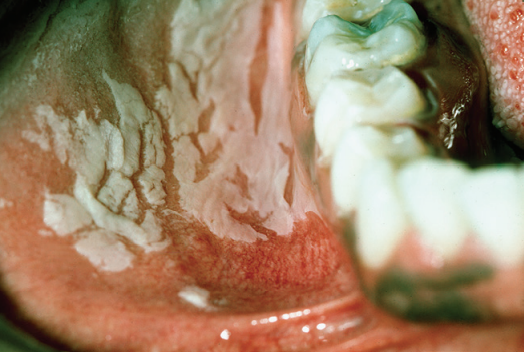

Reaccion Liquenoide por Amalgama Dental